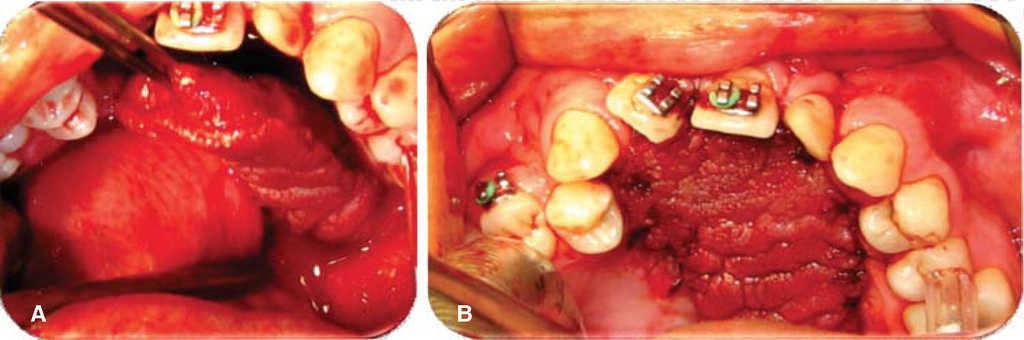

Oronasal fistula surgical closure was programmed with anterior based tongue distanced flap. Under general anesthesia with naso-tracheal intubation, palate and donor site were infiltrated with lidocaine and epinephrine at 2% and 1:100,000 to achieve hemostasis. A Digman type mouth prop was placed. A peri-fistular incision was executed with number 15 surgical blade and electric scalpel. The defect's borders were dissected and everted and then sutured with 910 4-0 polyglactine, 100% closure was achieved in the nasal mucosa plane. Nasal irrigation was undertaken with physiological solution, no egress of liquid was observed from the sutured defect. The Digman type mouth prop was removed and a Mackinson mouth opener was placed. The tongue was pulled with one 2-0 silk suture point at the tongue's tip. The anterior-based tongue flap was designed so as to be of a size 20% larger than the defect and with an approximate length of 5 cm, taking great care to cover the whole defect and avoid tension. Hemostasis was achieved with electrocautery and with polyglactin 910 sutures. Suturing of donor site was executed in two planes with 4-0 polyglactin 910; no hematomas were observed. The tongue flap was rotated over the defect and sutured over the defect borders with polyglatin 910 simple stitches. Surgical event was completed without complications or accidents (Figures 2, 3, 4). No inter-maxillary fixation was applied since, due to his age, the patient was considered to be cooperative.

Figure 2 A. Peri-fistular incision design. B. Peri-fistular incision with electric scalpel. C. Nasal mucosa dissection. D. Nasal plane suture and closing.

Figure 3 A. Design of anterior-based tongue flap. B. Incision with number 15 scalpel blade. C. Flap dissection at 7mm thickness including mucosa and muscle. D. Dissected flap. E. Suture of donor bed.

Figure 4 A. Rotated and everted tongue flap in the surgical bed. B. Presentation of tongue flap in surgical bed.